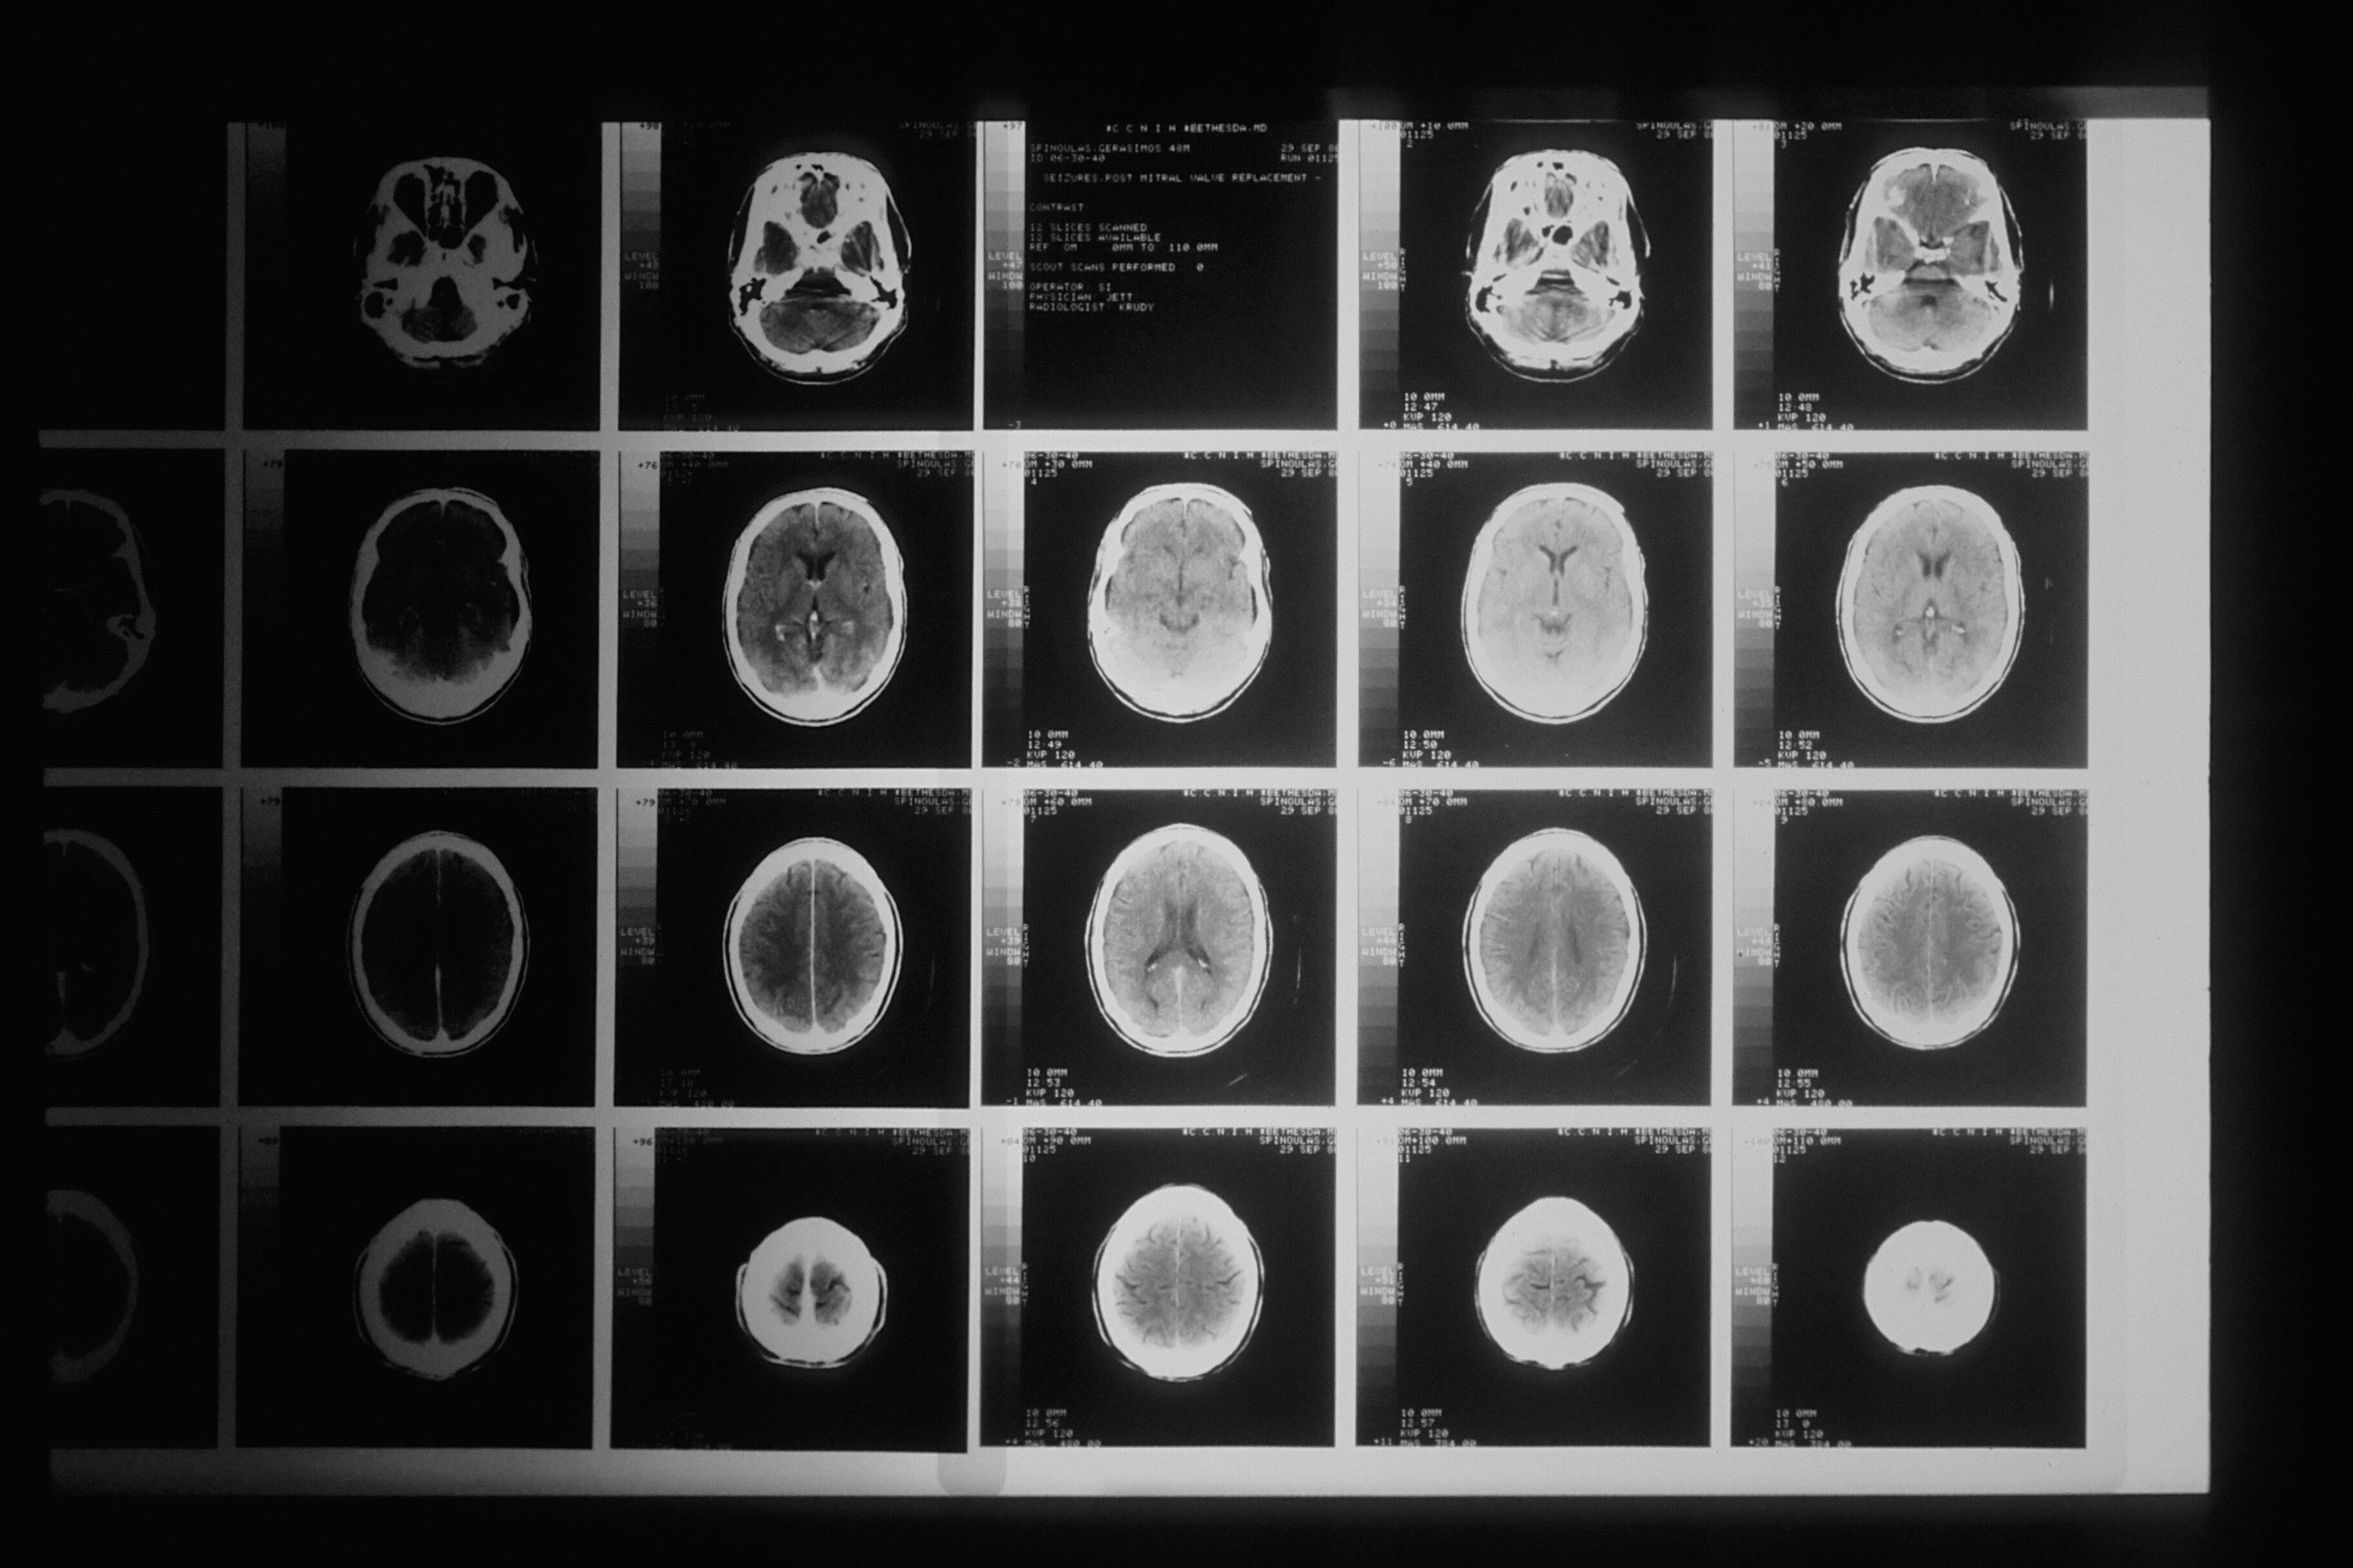

36-летняя женщина по имени Сара больше пяти лет пыталась бороться с тяжёлой депрессией, но ничего не помогало. Тогда она согласилась на то, чтобы ей в мозг вживили электроды.